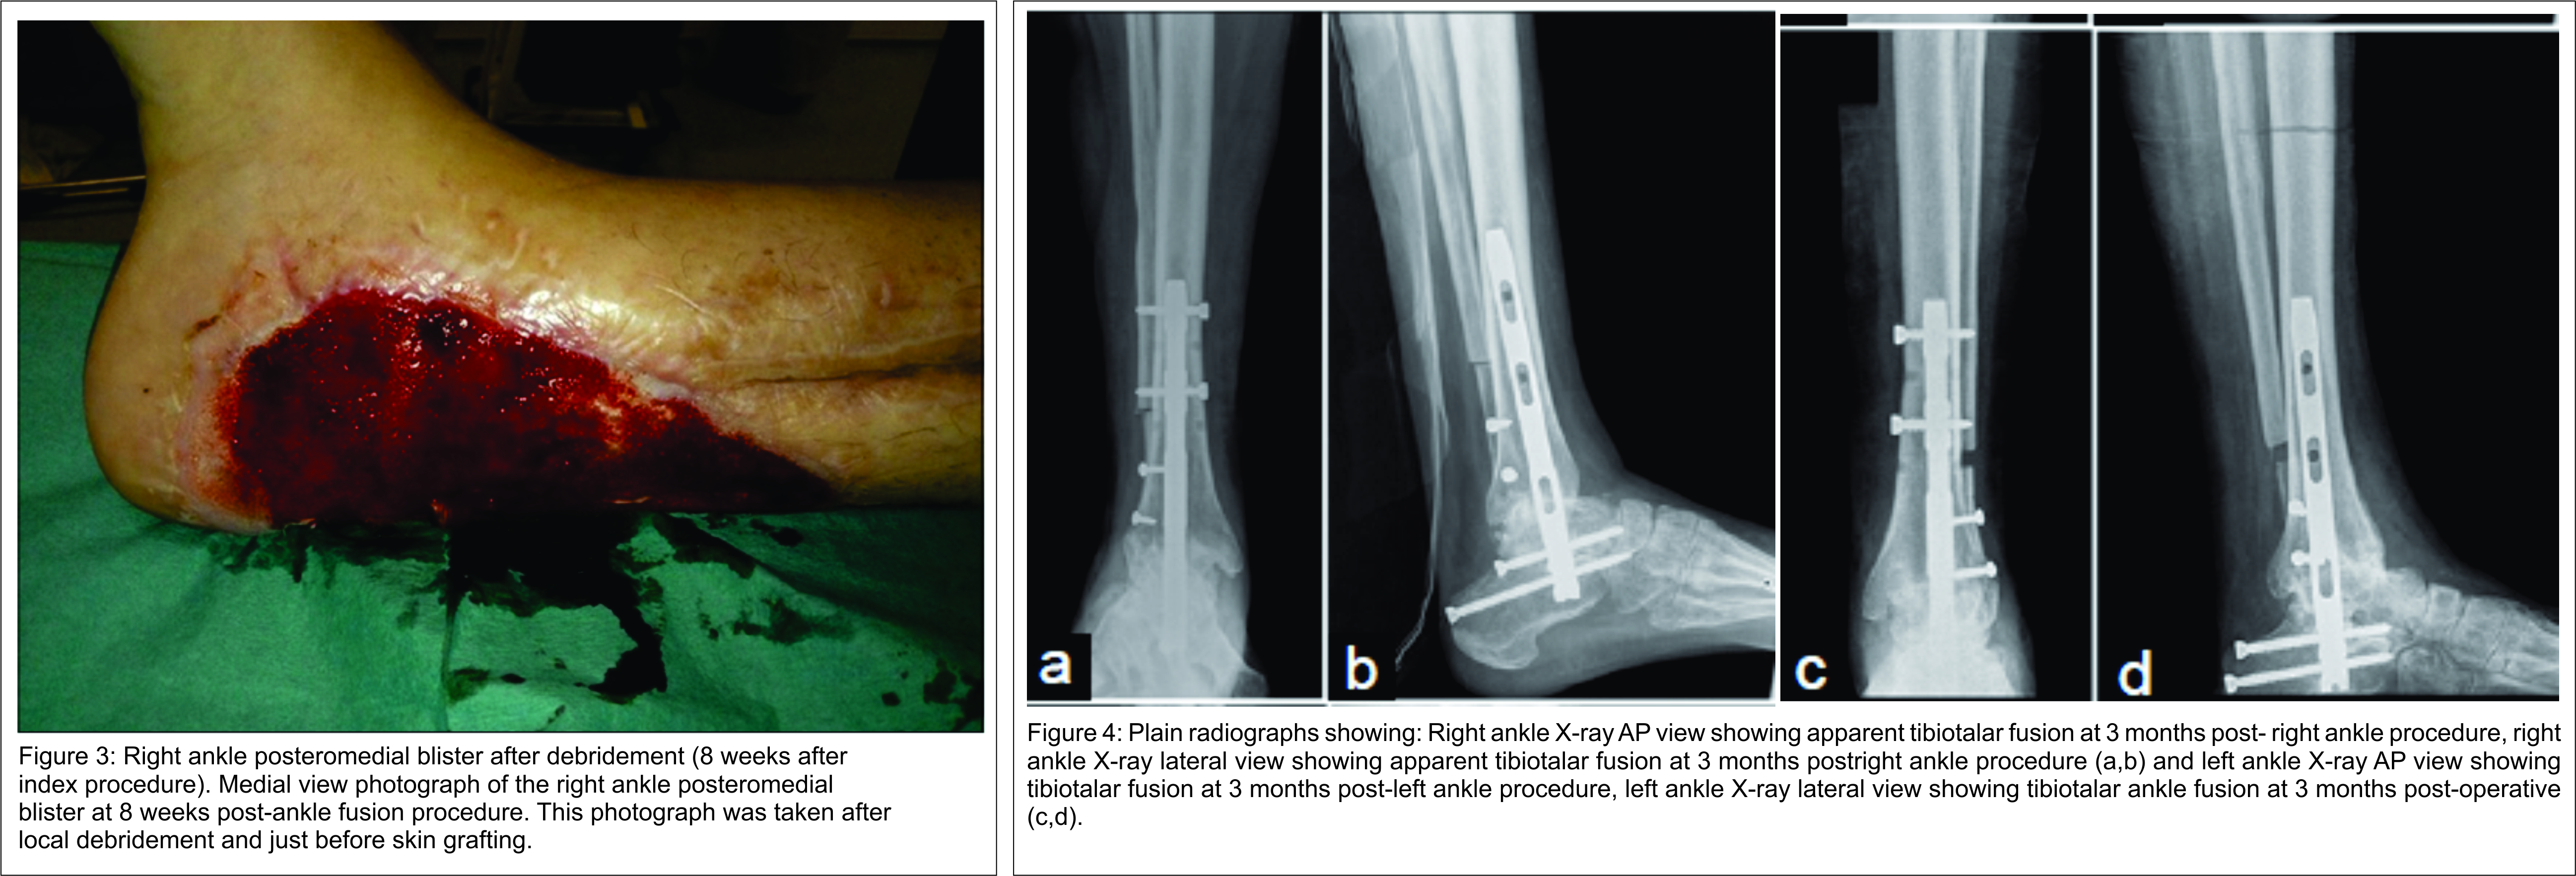

On examination, she presented a bilateral severe stiff equino-cavo-varus-adductus deformity with retraction due to subcutaneous and muscle scarring and neurological deficit. Claw hallux and lesser toes were also present bilaterally. Plantigrade weight bearing was not possible (Fig. 1). American Orthopaedic Foot and Ankle Society (AOFAS) score was 20 points. Plain radiographs showed bilateral equinovarus ankle deformity with supinated feet (Fig. 2). Achilles, posterior tibial, and flexor digitorum longus tendons lengthening were performed by medial approach associated to right tibiotalocalcaneal arthrodesis with a retrograde locked intramedullary nail (PANTA® – IntegraTM) by lateral approach. Distal fibula bone was used as an autograft. At 8 weeks of follow-up, plastic surgery applied a free skin graft over a persistent post-operative medial blister (Fig. 3). Apparent fusion was obtained at 3 months postoperatively (Fig. 4). At 6 months after the initial surgery, fusion surgery of the left ankle was performed in exactly the same fashion. As in the first procedure, clinical and radiological follow-up was done at 2, 6 weeks and every 3 months. Surgical wound dehiscence was the short-term complication and was resolved with dressing changes at 6 weeks post-operative. Fusion was obtained at 3 months postoperatively (Fig. 4).

At 12 months after the first surgery, we documented recurrent dorsal proximal interphalangeal (PIP) joints inflammation with shoe wear. Right foot Moberg osteotomy, resection arthroplasty of PIP joints, and flexor tendon tenotomy of all the lesser toes were performed. Left foot Moberg osteotomy, PIP joints fusion of the 2nd and 3rd toes with intramedullary guide implant (Ipp-On® – IntegraTM), PIP joints resection arthroplasty of the 4th toe, and flexor tendon tenotomy of all the lesser toes were performed 14 months after the index surgery. Hardware-related pain caused Moberg osteotomy staple removal at 6 weeks post-operative (Fig. 5). The rehabilitation protocol included progressive weight-bearing with walking boots and lower limb drainage for 6 months. Prophylactic human immunoglobulin therapy was initiated after the last surgery. She regained walking capacity with balanced shoes and returned to work 4 months after left foot surgery. AOFAS score improved to 61 points. No toes related complaints, pressure ulcers or terminal necrosis of the toes were found. At 24 months after initial surgery, she complained of right ankle pain de novo with weight bear and local swelling. Radiologically, failed arthrodesis with tibiotalar and subtalar bone reabsorption, peri-implant proximal radiolucency, and distal calcaneus screw fracture were shown. No local drainage or blood test infection parameters were found. Only symptomatic treatment and nonsteroidal anti-inflammatory drugs were prescribed. At 38 months of follow-up, the patient refers no significant right ankle pain, and no SCLS attacks recurrence was registered (Fig. 6).